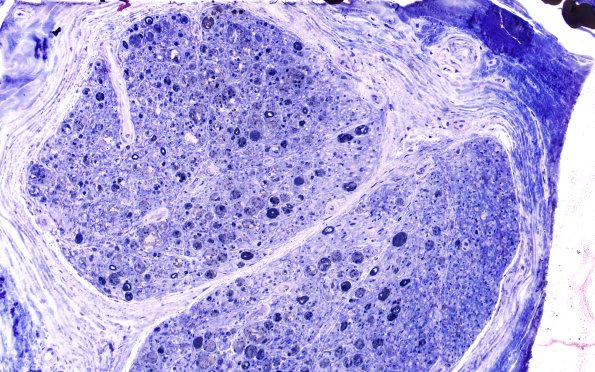

Washington University Experience | PERIPHERAL NEUROPATHY | 7A GUILLAIN-BARRE SYNDROME (GBS) | 4D1, fulminant (Case 4) Plastic 20X

4D1,2 Plastic sections show a variable appearance including marked axonal degeneration. Analysis of this area showed no residual myelinated axons, only degenerated axons. (Plastic sections)